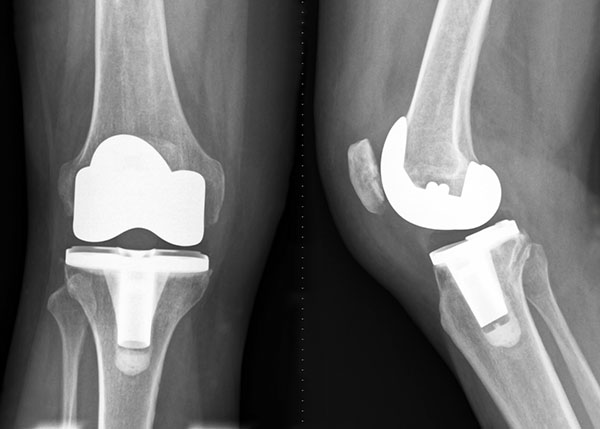

Knee Replacement

knee replacementThe knee joint consists of a layer of smooth cartilage on the lower end of your femur (thighbone), the upper end of the tibia (shinbone) and the undersurface of the patella (kneecap). This cartilage serves as a cushion and allows for smooth motion of the knee. Arthritis is a wearing away of this cartilage, which eventually wears down to bone. Rubbing of bone against bone causes pain, swelling and stiffness. For patients with significant arthritis who have failed conservative treatment, your surgeon may recommend joint replacement surgery.

Surgeons don’t actually replace the joint as is commonly thought. Instead, your surgeon replaces the damaged cartilage found at the end of the bones in your knee joint. This is done with a metal alloy on the femur (thighbone) and a medical grade plastic spacer on the tibia (shinbone) and patella (kneecap). This creates a new smooth cushion and a functioning new joint. The implants are designed to restore function and eliminate as much discomfort as possible while allowing the patient to return to a more active lifestyle.

Rehabilitation and walking begin the day after surgery, and hospital stay is typically just one overnight. Therapy will begin in the hospital and usually continues after discharge with home PT. Joint replacement surgery of the knee has been extremely successful in helping patients with arthritis return to their normal activities and relieve their discomfort.